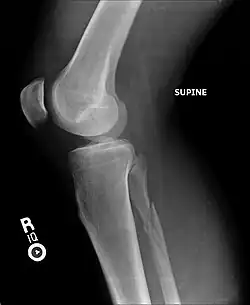

| Radiograph showing a Maisonneuve fracture of the proximal fibula | |

X-ray, CT, or MRI scans can be used to diagnose the extent of the Maisonneuve fracture's damage and determine whether it is a simple or comminution fracture.[8] During diagnosis, a supination-external rotation pattern of injury may also be concluded if there is an isolated fracture of the posterior tubercle of the tibia.[9]